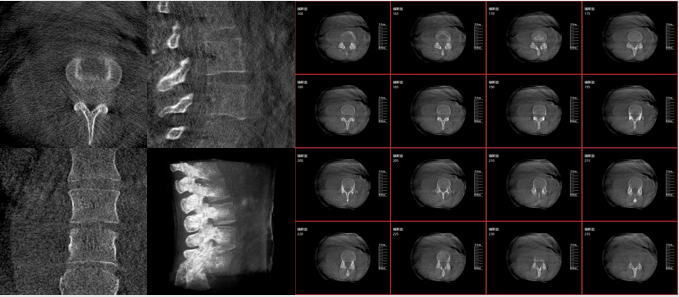

術(shù)中三維影像

而三維影像的MPR圖像組可以通過(guò)不同平面的切分,使成像區(qū)內(nèi)更豐富的信息得以呈現(xiàn)。尤其是二維影像無(wú)法涉及的橫斷面,提供了另一個(gè)空間維度的信息量。

作為使用者,醫(yī)生在手術(shù)中雖然有術(shù)前的影像作為判定依據(jù),但每一臺(tái)手術(shù)都具有獨(dú)特性,需要術(shù)中三維影像提供的實(shí)時(shí)信息,作為術(shù)中診療操作的基礎(chǔ)。

在MPR圖像中,冠狀面、矢狀面和橫斷面的信息大大提高了醫(yī)生對(duì)于病灶區(qū)以及手術(shù)效果的判定。